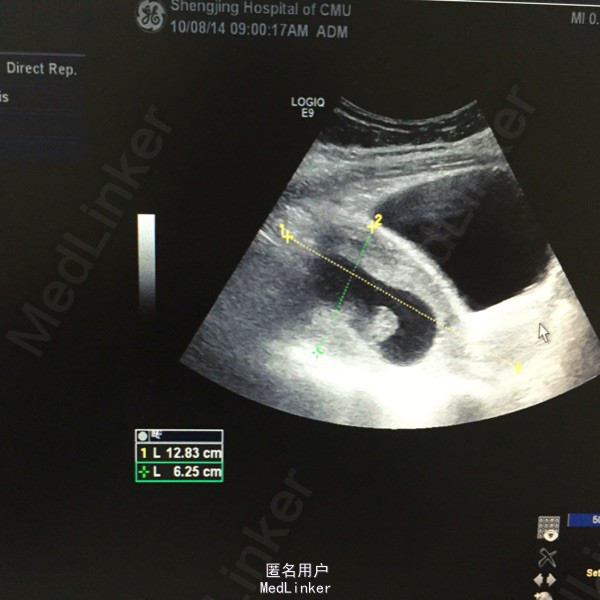

盆腔彩超:子宫前位,宫体增大,宫内可见3.3*1.9*1.7cm妊娠囊,其内可见卵黄囊及8mm胎芽,见胎心搏动,双侧卵巢可见,于子宫左侧可见一3.0*2.3cm妊娠囊,其内卵巢囊及7mm胎芽,可见胎心搏动。超声提示:宫内早孕,合并左附件区异位妊娠。